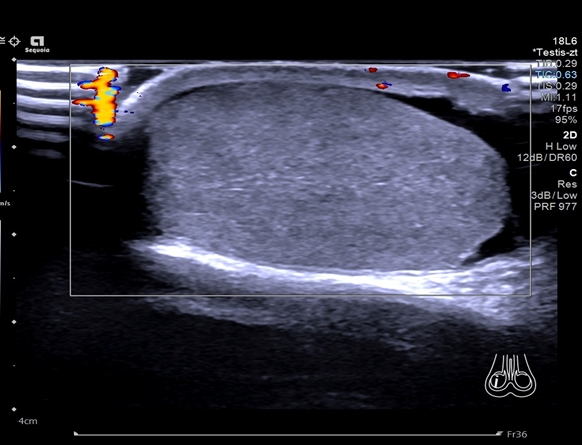

那是一个风雨交加的下午,快下班了,来了一个20岁的小伙做睾丸彩超,询问病史得知男生的“蛋蛋”已经疼了一天,而且是越来越痛,我心中顿感不妙,彩超一看男生左侧的睾丸已经没有血流信号了。我立刻告知泌尿外科医生,紧急手术,术中见左侧精索扭转720°,睾丸明显坏死,无保留价值,患者家属只能痛心选择切除。

2.间接征象:因精索扭转缩短而睾丸位置抬高,睾丸长轴由正常的斜位扭转为横位,睾丸回声不均。彩色多普勒:双侧对比,早期患侧血流信号明显减少,晚期血流信号消失。